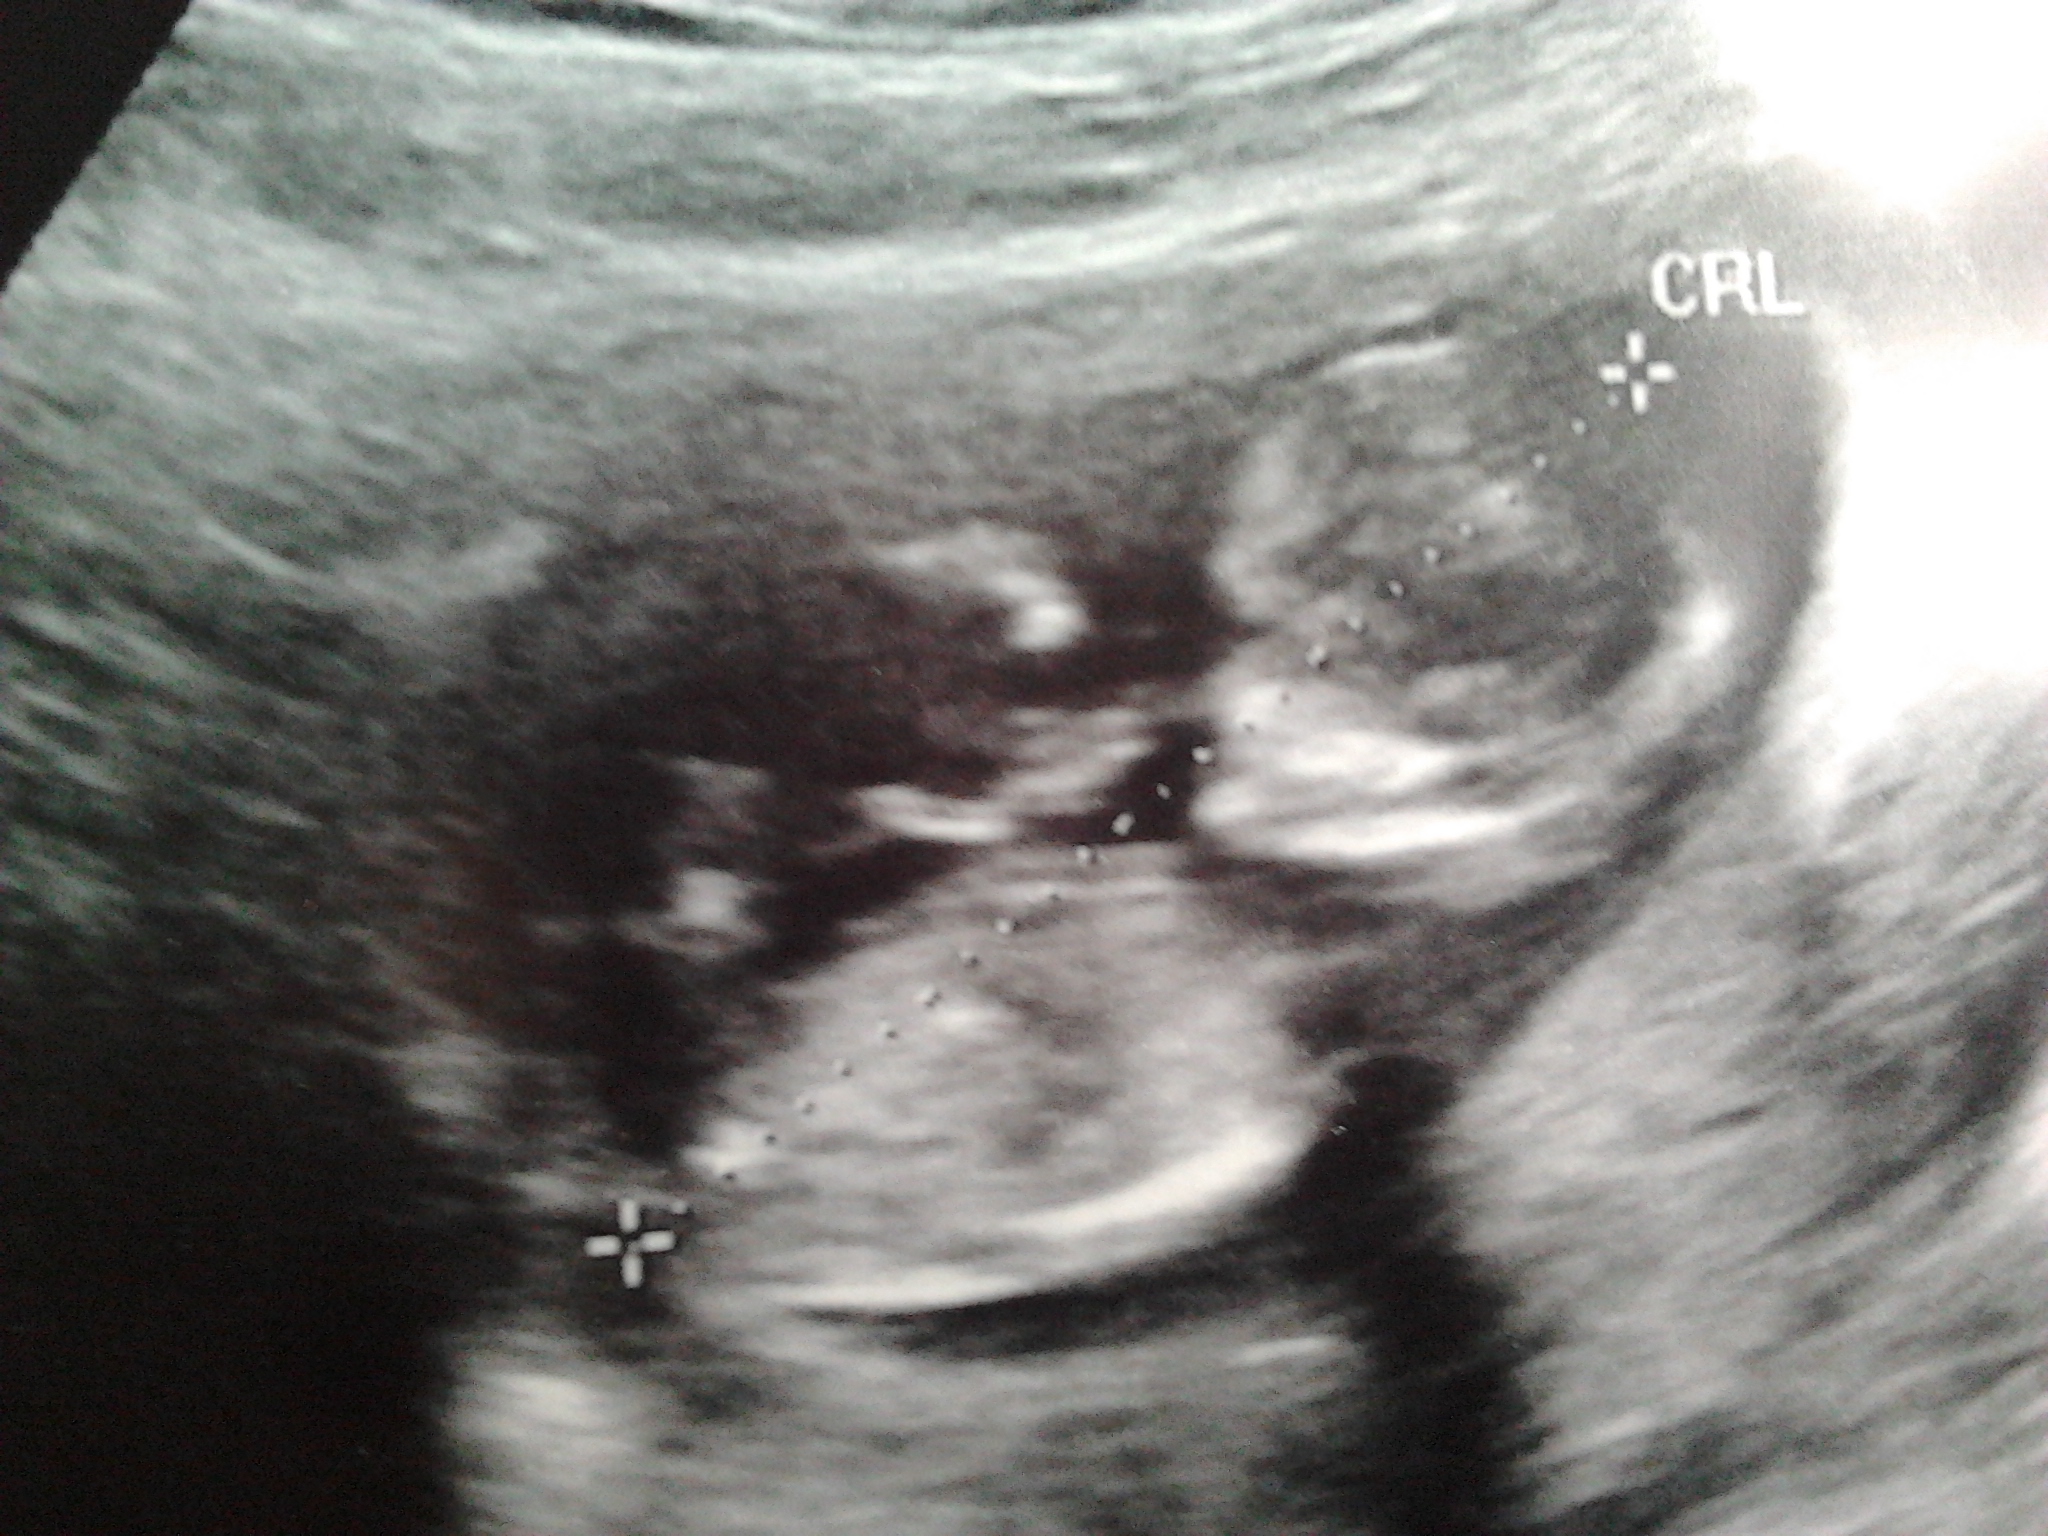

This is my ultrasound, taken yesterday, 12w5d.

Who can take a guess?Attachment 14538Attachment 14539Attachment 14540Attachment 14541